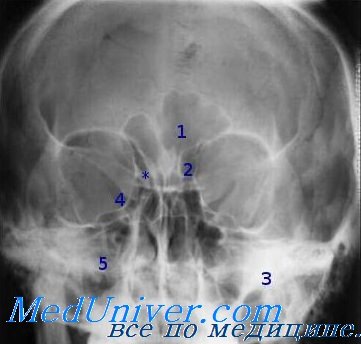

Рентгенография небного шва: Медицинские исследования и диагностика